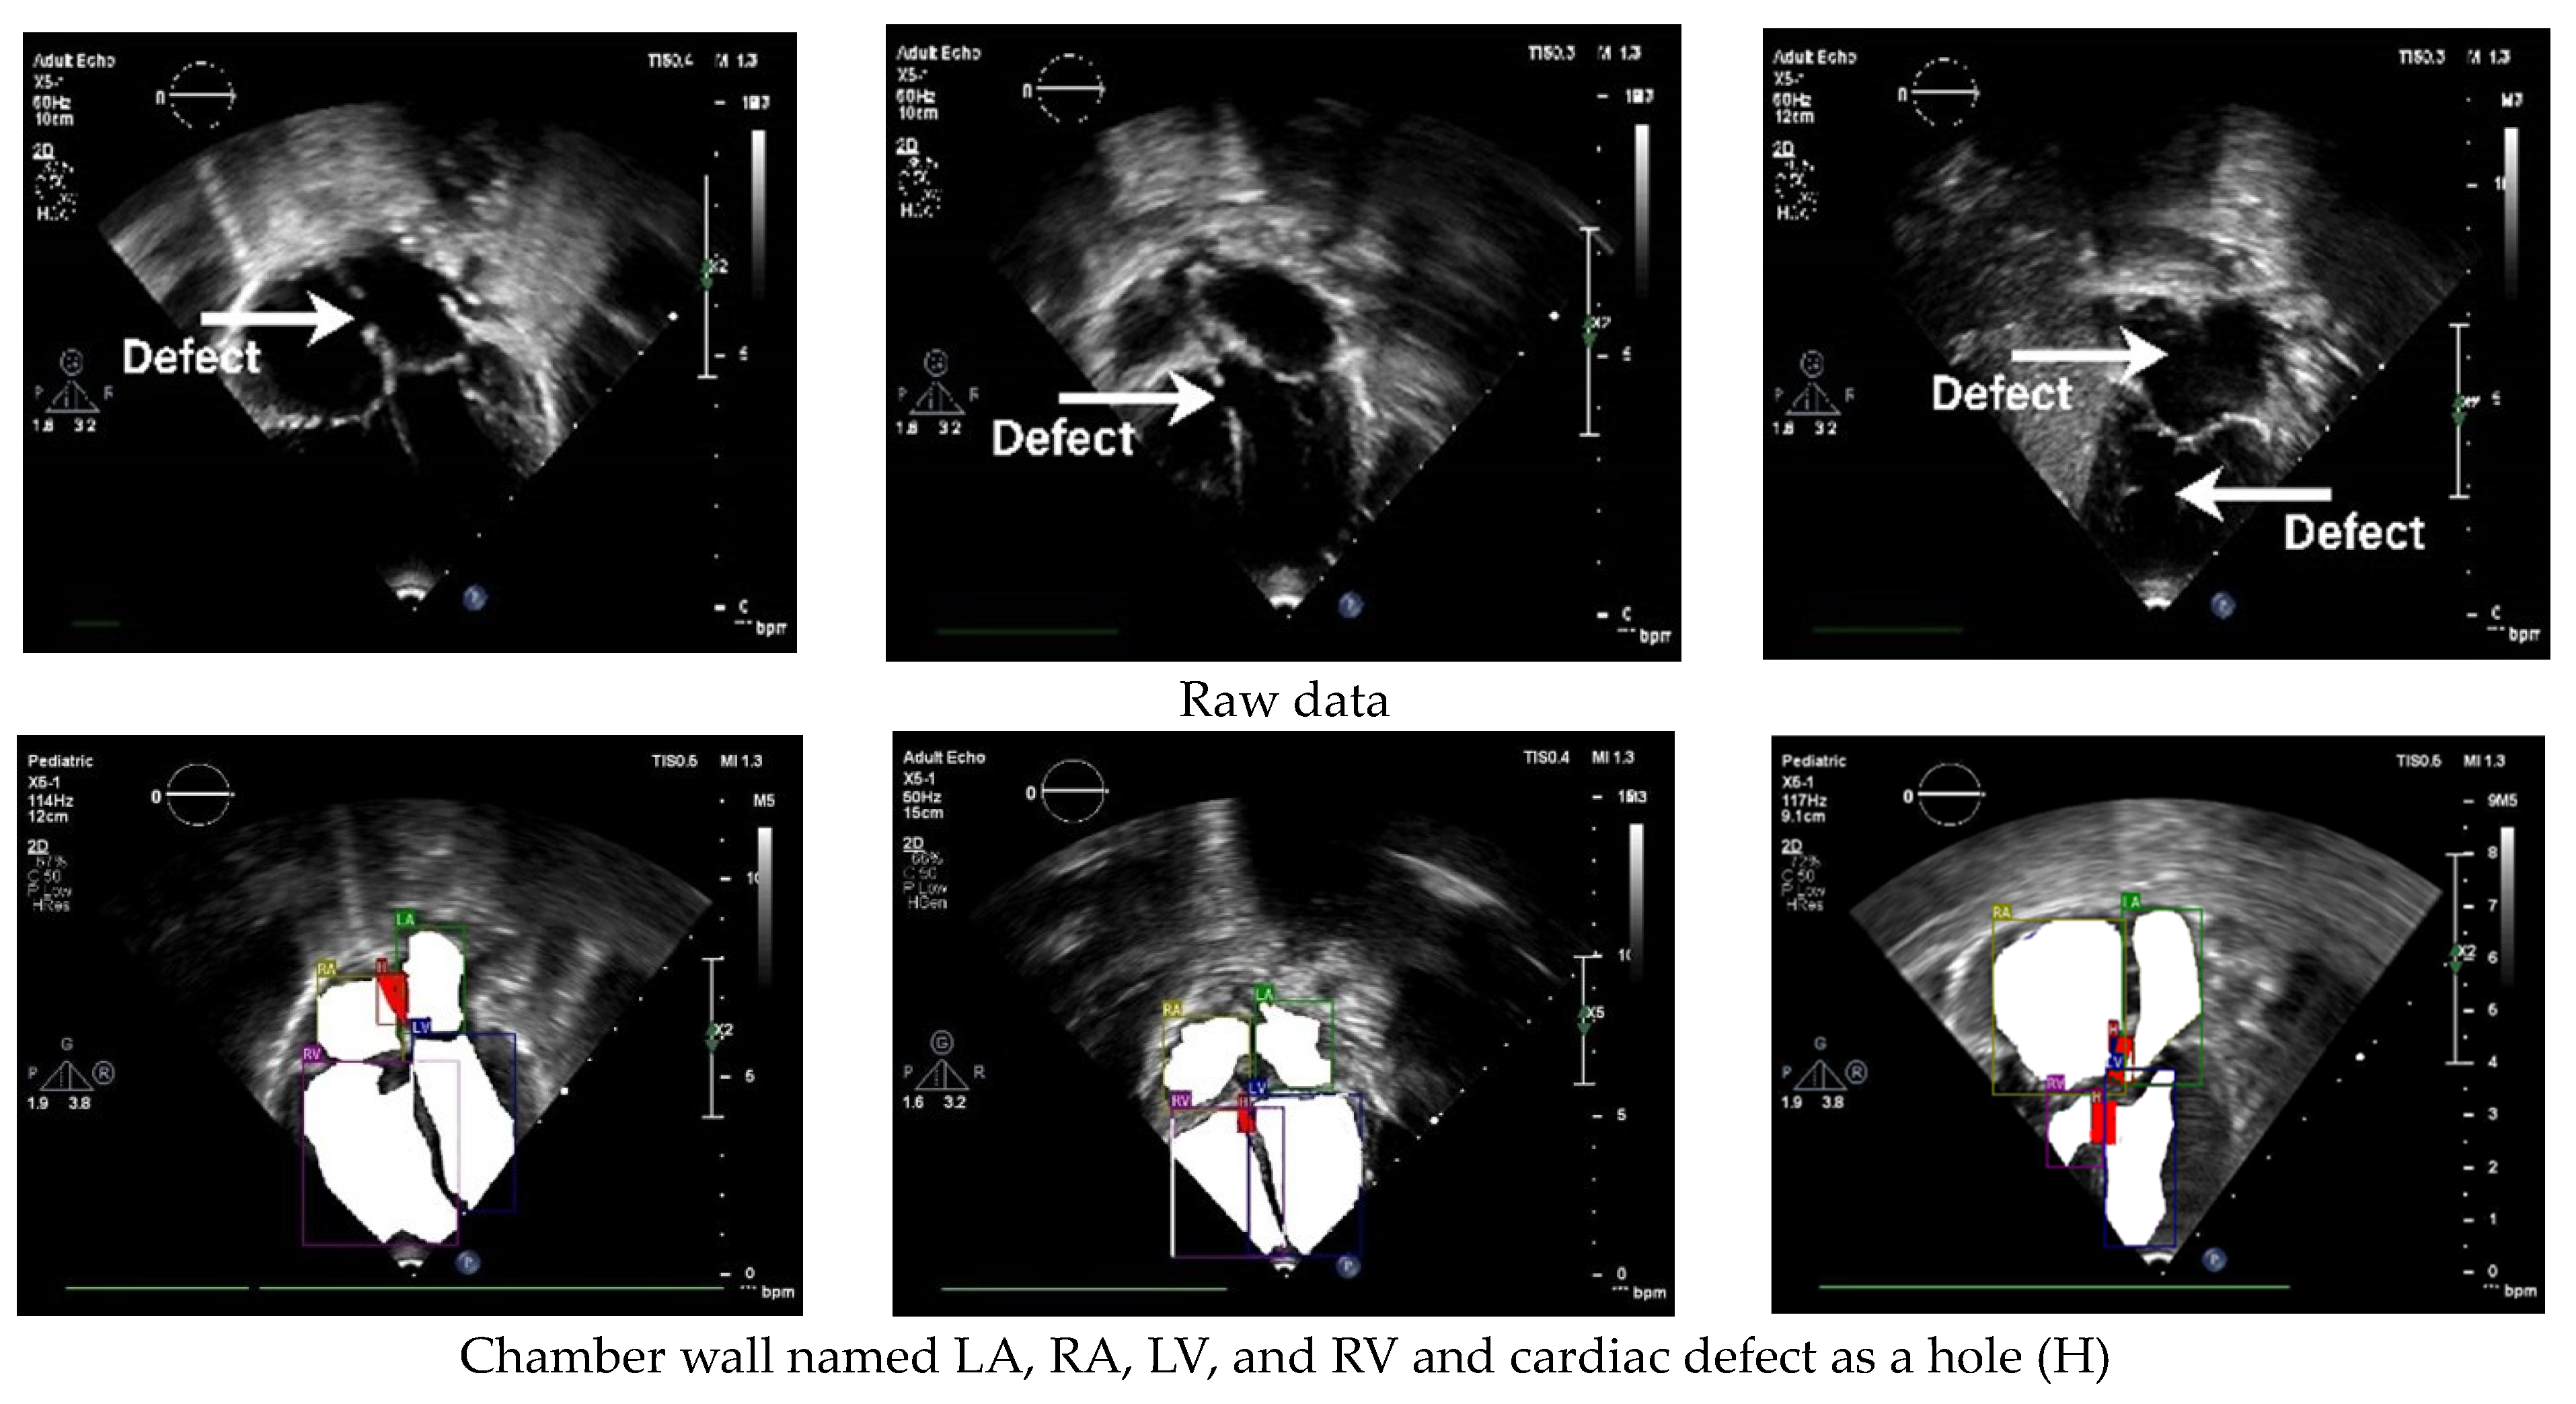

The standard cardiac view of US video recordings has consisted of A4CH, A5CH, PLAX, PSAX, and SC. Pediatric cardiologists rely on specific views when assessing a patient’s condition. The annotation of the three CSD conditions is presented in Figure 3 using LabelMe 5.3.1 software. The annotated sample results in showcasing the chamber wall area and the cardiac defect area. Atrial or ventricular areas are represented by the white regions, while the red region denotes a cardiac defect area.

Figure 3.

Annotation of chamber wall and cardiac defect.